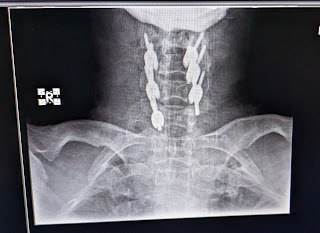

55/M Pyrexia under evaluation with cervical laminectomy 2 months back

Patient was apparently asymptomatic 2 months back after which he had an RTA during which he had cervical cord stenosis and was operated with cervical cord laminectomy i/v/o weakness of both upper and lower limbs. After which patient was on physiotherapy and power improved gradually.Now patient had h/o burning sensation and numbness of whole body( paresthesia).

Pyrexia under evaluation with cervical laminectomy 2 months back